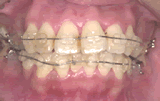

症例1/前歯が出ているのが気になる

【歯科手術中】

(器具を取り付けた状態)